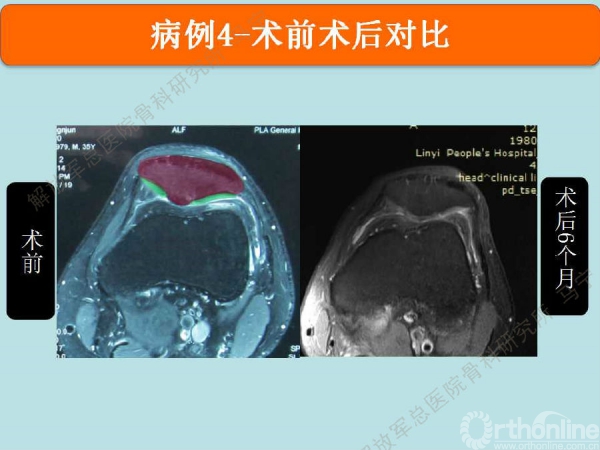

姜**:男,33岁 ,双膝疼痛,活动受限1年,曾经打过玻璃酸钠,效果都不理想,来我院行软骨修补术,MRI显示髌骨软骨下骨增生明显,并开始磨损滑车。

术中显示软骨损伤的面积比核磁上的范围要大很多。

术后3个月在当地医院复查MRI,软骨补片与正常软骨还存在GAP现象,冠状位隐约还能看见周围的轮廓。

术后6个月复查MRI,软骨修复的已经具备一定的厚度,软骨下骨没有明显水肿。增生的软骨下骨被去除后没有再进一步磨损滑车软骨。